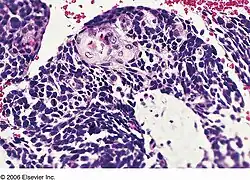

Combined small cell lung carcinoma containing a component of squamous cell carcinoma | |